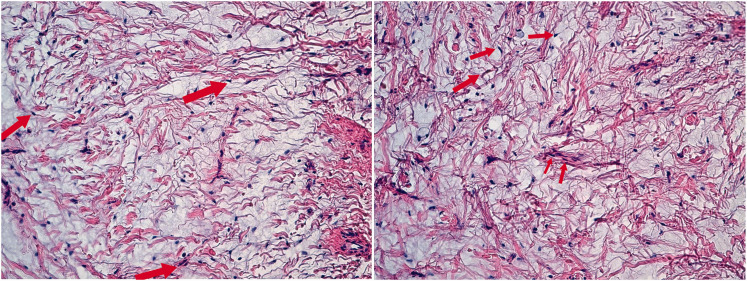

Desmoplastic fibroblastoma is a benign tumor. It was first reported by Evans in 1995 and is also known as collagenous fibroma. We encountered a case of desmoplastic fibroblastoma in clinical practice, wherein a 2-year-old girl presented with the following specimen from the scalp-a piece of gray-white nonplastic tissue with a volume of 2 × 1.5 × 1 cm. The cut surface was gray-white, solid, and of moderate consistency. Microscopically, there were only a few tumor cells, composed of spindle-shaped and stellate fibroblasts embedded in a dense collagenous or myxoid matrix, with minimal cellular atypia. The patient underwent surgical procedures for resection and is recovering well. This report provides an opportunity for experts and scholars to learn and communicate together. A new breakthrough has been achieved with regard to the age range of onset for this disease.